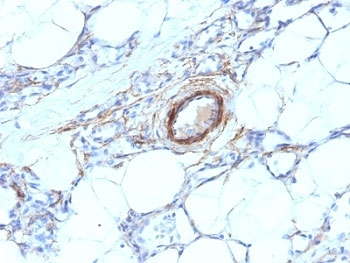

IHC: Formalin-fixed, paraffin-embedded human angiosarcoma stained with SMMHC antibody (MYH11/923).